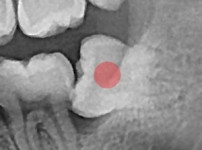

严重龋坏的智齿